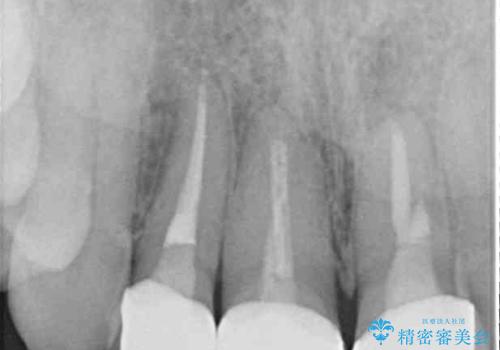

- 以前に装着した前歯のクラウンの縁が見えていることを気にして来院された患者様です。

根尖部に病変のある2歯は事前に根管治療を行い、オールセラミッククラウンにて補綴することとしました。